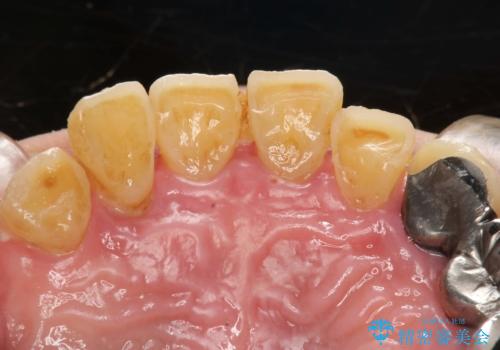

虫歯だらけ、歯周病 崩壊した口腔の再建 フルマウスリコンストラクション

- 歯周外科・インプラント・顕微鏡下根管治療などを含んだ総合的な治療を計画した。

様々な治療手段を高いレベルで同時に併行して行うことが必要でした。

かみ合わせの力が非常に強く、夜間の歯ぎしり・食いしばりもひどかったため、奥歯はメタルオクルーザルの設計でかぶせ物を製作しています。